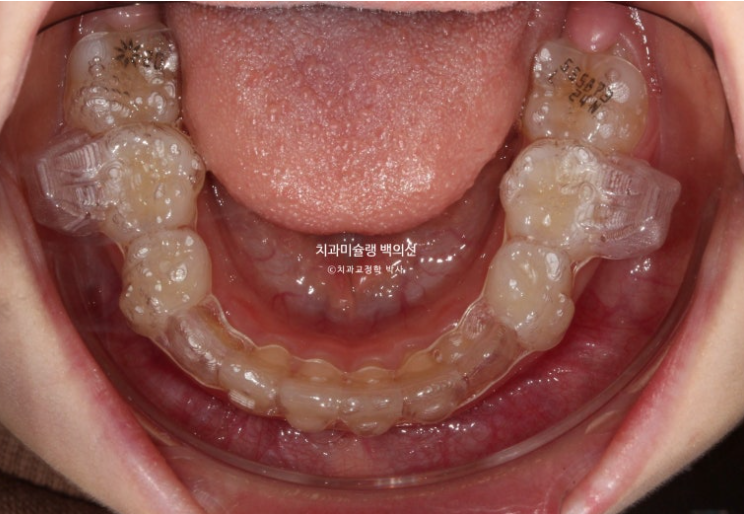

아랫니도 공간이 많이 부족합니다.

골격분석상 하악골 여성장을 동반한 무턱으로 진단되어 치료 목표는

-

악궁확장을 통한 덧니 해소

MA 기능으로 하악성장 유도

이 두가지가 되겠습니다.

손 엑스레이 성장판 분석한 결과 최대 성장기가 시작되는 시점이라 타이밍도 아주 좋습니다.

인비절라인 퍼스트로 권유드렸고 치료를 시작했습니다.

치료계획은 전반부의 악궁확장 및 덧니해소 단계와 후반부의 MA를 통한 하악성장 유도 두단계로 나뉩니다.